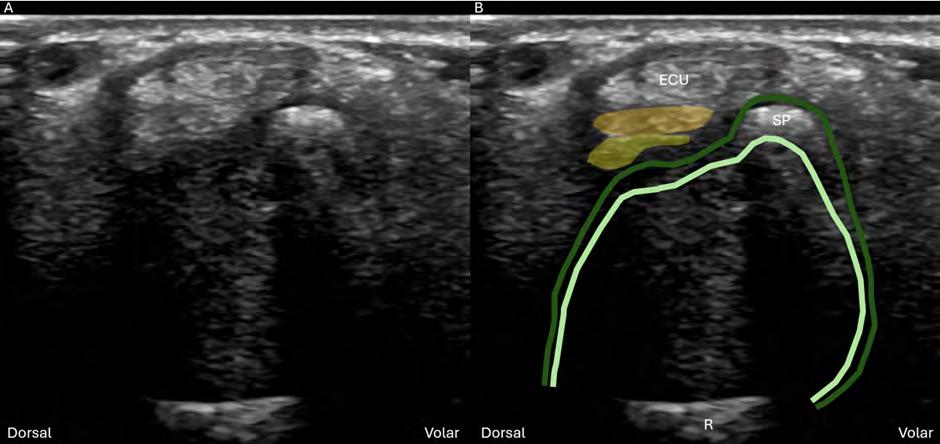

The articular disc is the major component of the TFCC and appears hypoechoic on ultrasound. In transverse (Figure 1), it appears as a hypoechoic disc-shaped structure and in longitudinal, the disc can be seen thinning towards its radial aspect. Between the styloid process and the articular disc lie (from superficial to deep) the ulnar collateral ligament, meniscus homologue and the two limbs (superficial and deep) of the radioulnar ligament. The layering and relationship between the various components, styloid process, ulnar fovea and ECU, serve as important reproducible sonographic landmarks in both longitudinal and transverse imaging.

Figure 1. Transverse sonogram of the articular disc at the level of the ulnar styloid process. (A) US and (B) superposed US images demonstrating the articular disc (blue shade), deep (dark green shade) and superficial (light green shade) limbs of the radioulnar ligament, meniscus homologue (yellow shade), ulnar collateral (orange shade). R: radius; ECU: extensor carpi ulnaris; SP: styloid process; US: ultrasound.